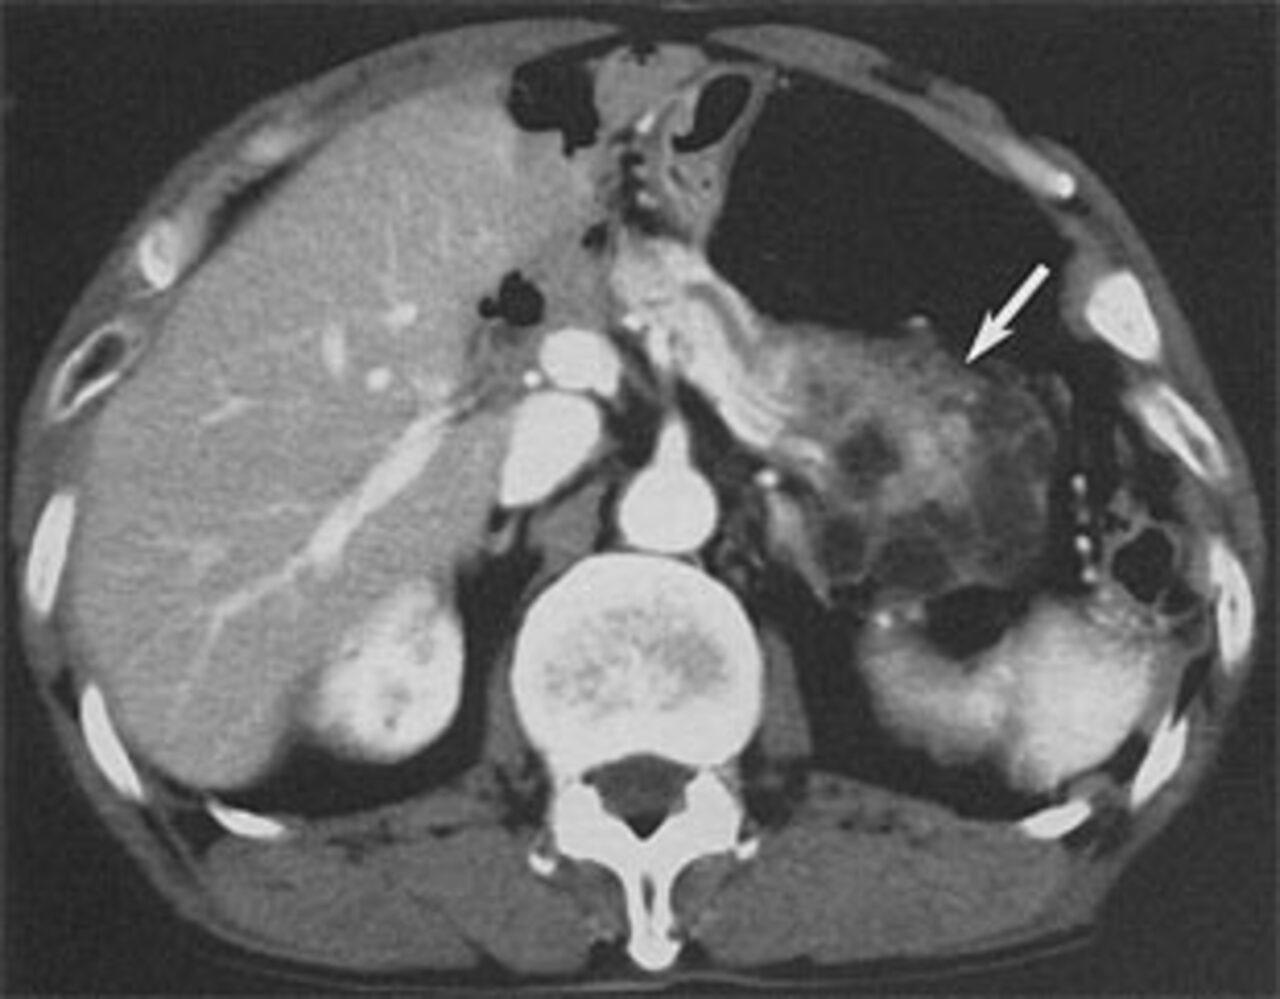

術前の造影画像や手術図式説明写真をUPしました

胃は全摘出、膵臓は必要部位を!肺は、暫く推移を見る